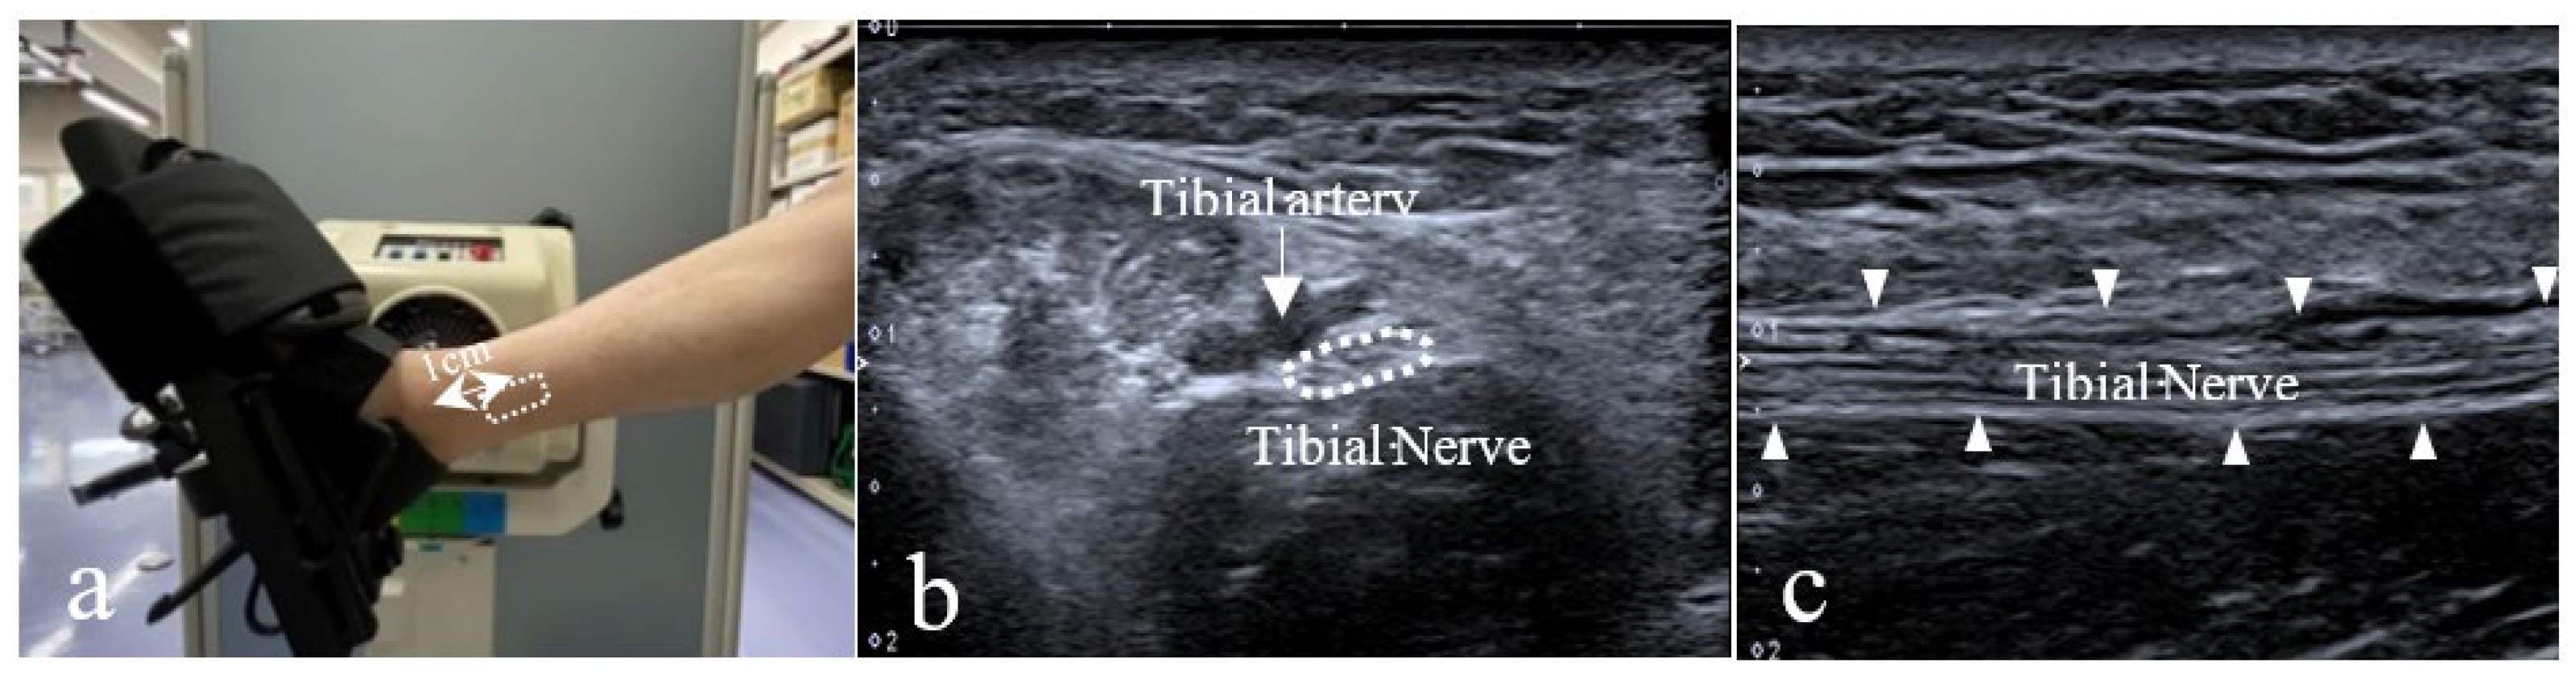

2.2. Ultrasound Image Capturing Method